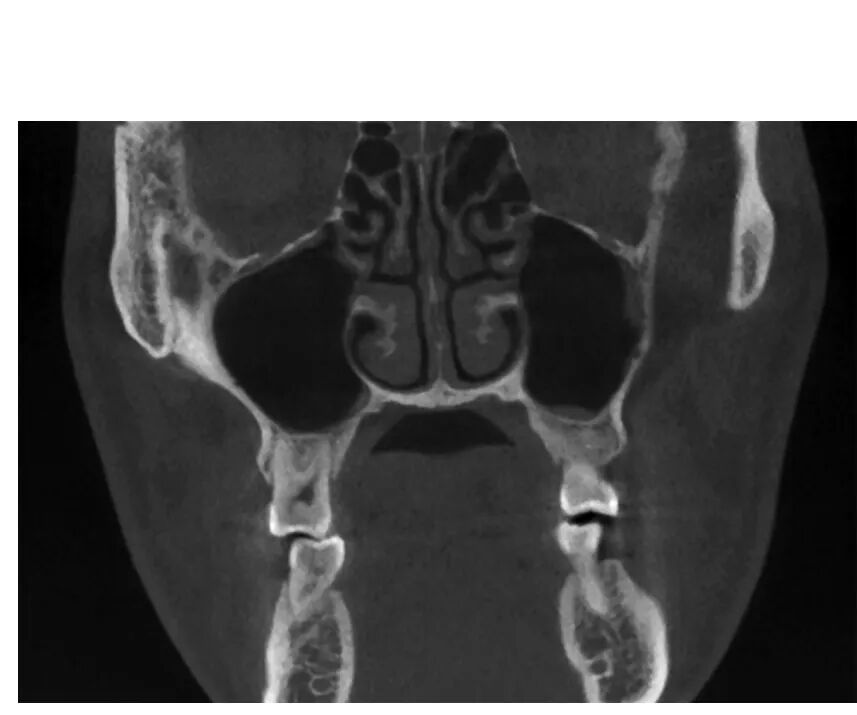

CBCT图像显示上颌窦是一个形状不规则,大小也不尽相同的腔,矢状位上是一由上、下、前、后壁构成的类似四方形或者梯形结构(图1-1-12)。冠状位上可见上颌窦上、下、内、外壁,形态多不规则(图1-1-13)。水平位可见前外、后外、内壁,中份多为类三角形,两端形态多不规则(图1-1-14)。上颌窦腔的容积为9. 5~20ml,平均为14. 75ml。不同人上颌窦形状和大小差别较大,同一个体双侧上颌窦形态基本对称(图1-1-15),但也存在同一个体两侧上颌窦形状和大小有差异(图1-1-16)。

CBCT冠状位可见上颌窦上、下、内、外壁,窦腔形态不规则